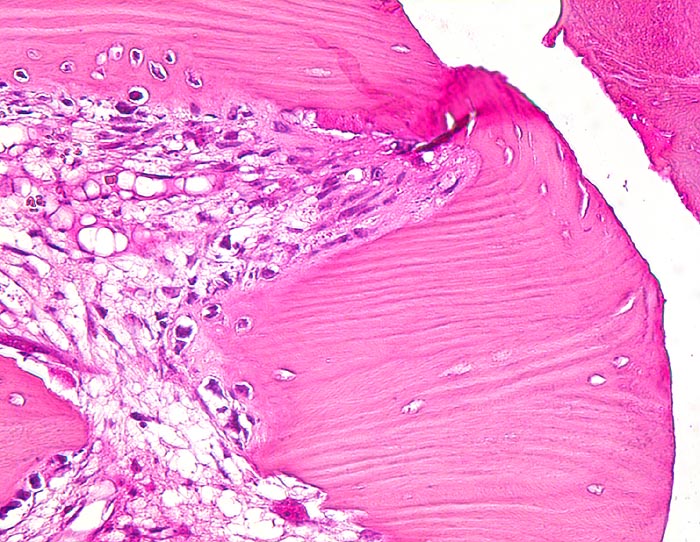

Morphologische Merkmale:

• Über dem Frakturspalt senkrecht auf die Frakturlinie ausgerichtete Faserknochenbälkchen mit Osteoblastensaum und ausgedehnte Bezirke von neugebildetem Knorpel.

• Devitalisierter ortsständiger Knochen mit leeren Osteozytenhöhlen angrenzend an den Frakturspalt.

• Enchondrale Ossifiktation des neugebildeten Knorpels.